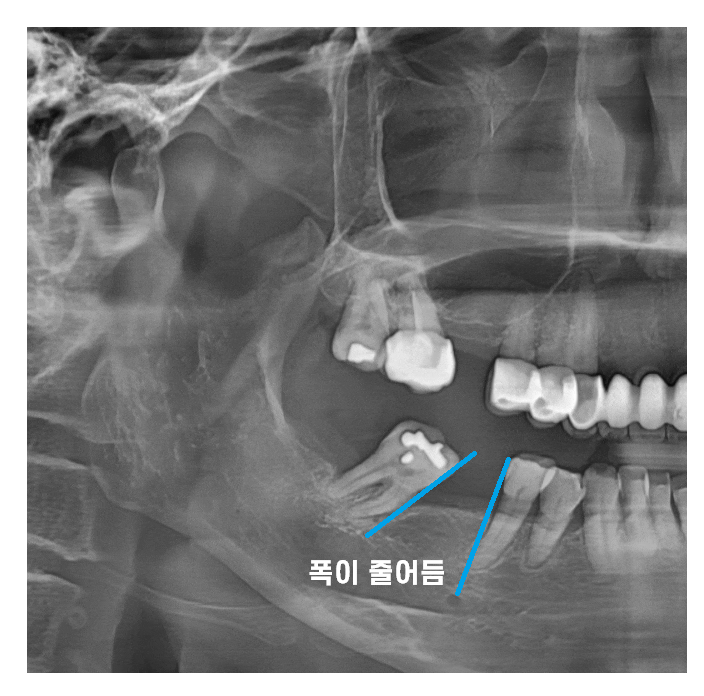

치아가 빠지게 되면 다른 치아들이

빈 공간으로 이동하면서 배열이 엉킬 수 있습니다.

오늘 환자분도 빠진 어금니 방치하다가

멀쩡한 큰 어금니가 많이 기울어졌습니다.

뿌리가 이동을 하기에

겉으로 보기에는 많이 쓰러졌는지

모르는게 문제입니다.

x-ray를 찍어보면

치아가 기울어진게 보이는데 말이죠

빠진 어금니 방치하다가

치아가 쓰러져

해당 환자분은 임플란트를 심을 공간이

부족하셨습니다.